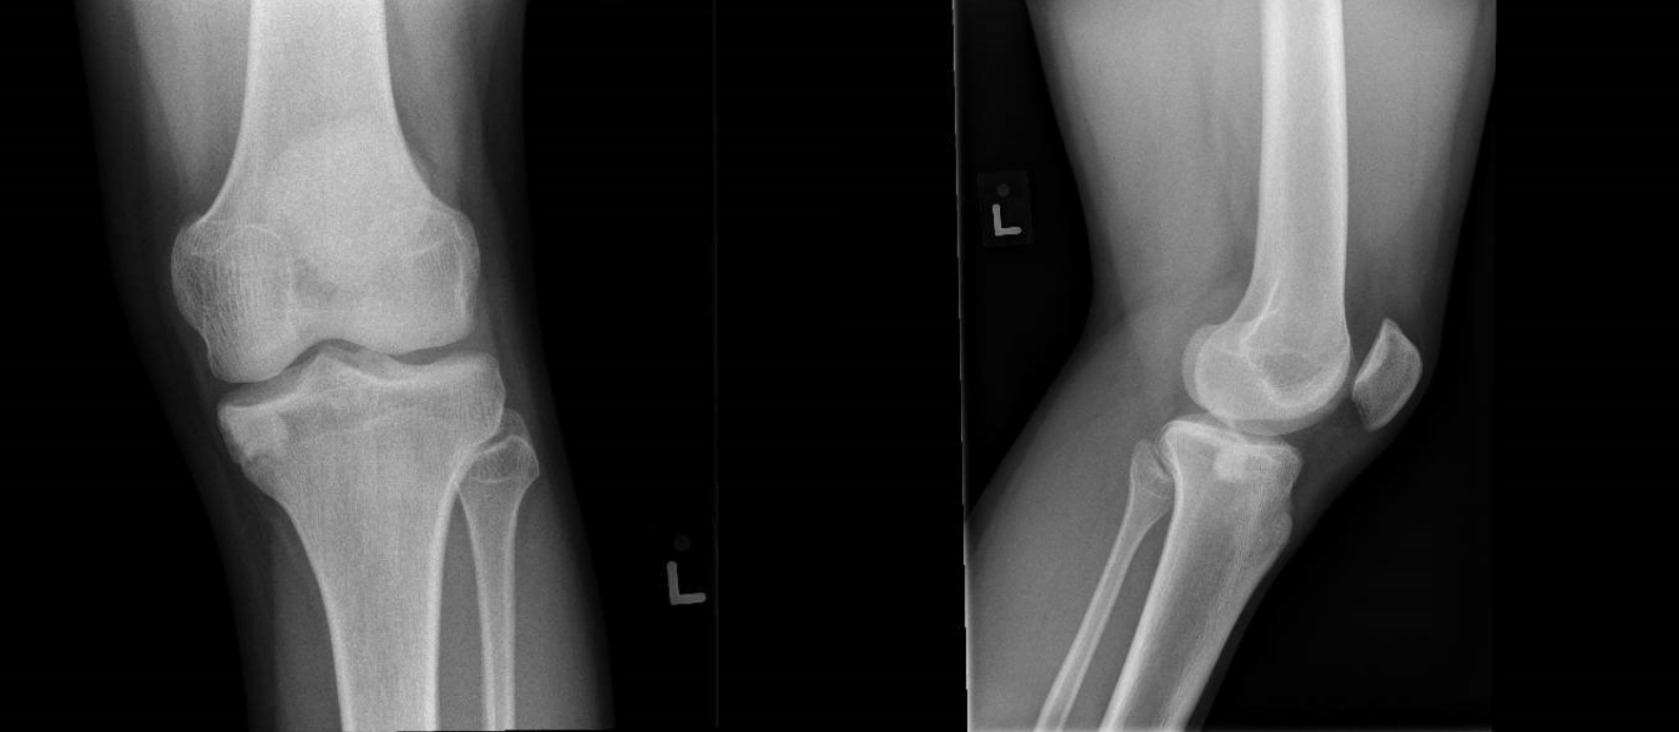

On examination, the only notable finding was severe tenderness along the left medial joint line. A left knee radiograph and magnetic resonance imaging (MRI) were ordered.

An MRI of the left knee was performed using fast spin echo techniques. A hyperintense lesion measuring 1.2 cm × 0.7 cm × 0.9 cm along the cartilage of the medial tibial plateau was identified, which was associated with significant marrow edema extending to the tibial eminence (Fig. 1). The tibial lesion was not well appreciated on the radiograph performed. Such a finding would point toward an undefined osteochondral lesion based on its site and characteristics, and given the profile of an avid soccer player, physical findings, and considering more epidemiologically common conditions, the diagnosis of a benign osteochondral lesion was made.

Post-operatively, the recovery seemed to go as planned. The patient was fitted in a Breg® Knee Brace (Breg, Inc., Carlsbad, CA, USA) and advised to maintain partial weight bearing with crutches, while also adhering to a range of motion restriction 0 - 90 degrees for 1 month. During a follow-up 1 month post-operatively, there was significant improvement in pain and full range of motion with slight knee discomfort on weight bearing activities. Mild quadriceps atrophy was also noted and the patient was advised to continue physiotherapy for strengthening while avoiding any overly strenuous activity or sports. When reviewed 2 months later, an x-ray of the left knee showed a persistence (Fig 2), but a seeming reduction in size of the tibial lesion.

When considering plain radiographs, chondroblastomas are typically characterised as well-circumscribed, lytic lesions with a sclerotic rim, often with central calcifications indicative of chondroid matrix mineralisation (Grimm et al. 2017). Osteochondral lesions may initially present with subtle radiographic signs such as light radiolucencies and/or epiphyseal contour abnormalities. As both progress, they may exhibit a more defined border with better defined features - but in early stages, both lesions can appear similarly on radiographs, making them easily confused (Chau et al. 2021).